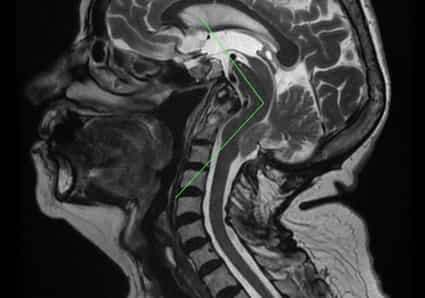

Abb. 1: Sagittale kraniozervikale MRT-Aufnahme mit Hirnstammkinking auf der Höhe des Pons und der Medulla oblongata – Rückenmark. Außerdem liegen eine Basilarinvagination, eine Odontoid-Retroflexion und ein Tiefstand der Kleinhirntonsillen vor. Hervorzuheben ist die Vergrößerung des suprazerebellären Raums, die die Traktionstheorie unterstützt und der Theorie einer Fehlbildung mit zu kleiner posteriorer Fossa widerspricht.

Die Diagnose und Beobachtung des Hirnstammkinkings erfolgt durch Bildgebung mittels Kernspintomographie (MRT), d. h. durch eine MRT-Untersuchung des Gehirns oder des Schädels (siehe Abb. 1).